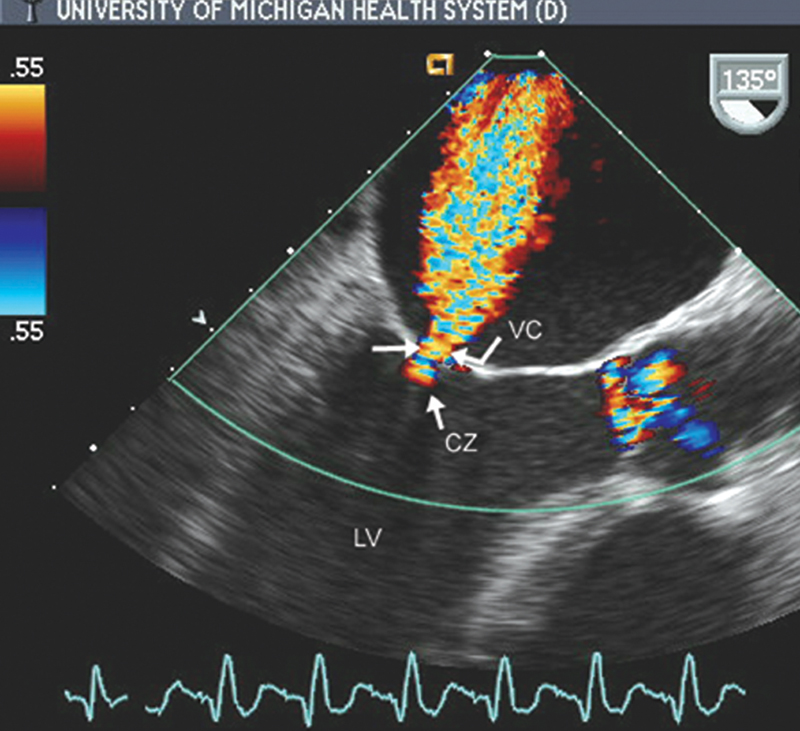

فحوصات تشخيصية لبعض امراض القلب والشرايين التاجية